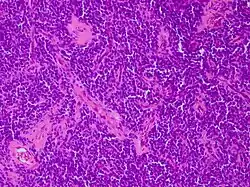

| Micrograph of an H&E stained section of a peripheral PNET. | |

Primitive neuroectodermal tumor is a malignant (cancerous) neural crest tumor.[1] It is a rare tumor, usually occurring in children and young adults under 25 years of age. The overall 5 year survival rate is about 53%.[2]

It gets its name because the majority of the cells in the tumor are derived from neuroectoderm, but have not developed and differentiated in the way a normal neuron would, and so the cells appear "primitive". PNET belongs to the Ewing family of tumors.